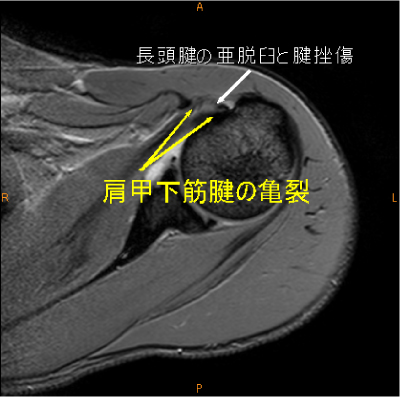

MRI所見

Hidden lesion症例(長頭腱亜脱臼、肩甲下筋腱損傷)

Hidden lesion(長頭腱亜脱臼+肩甲下筋腱断裂), 長頭腱亀裂